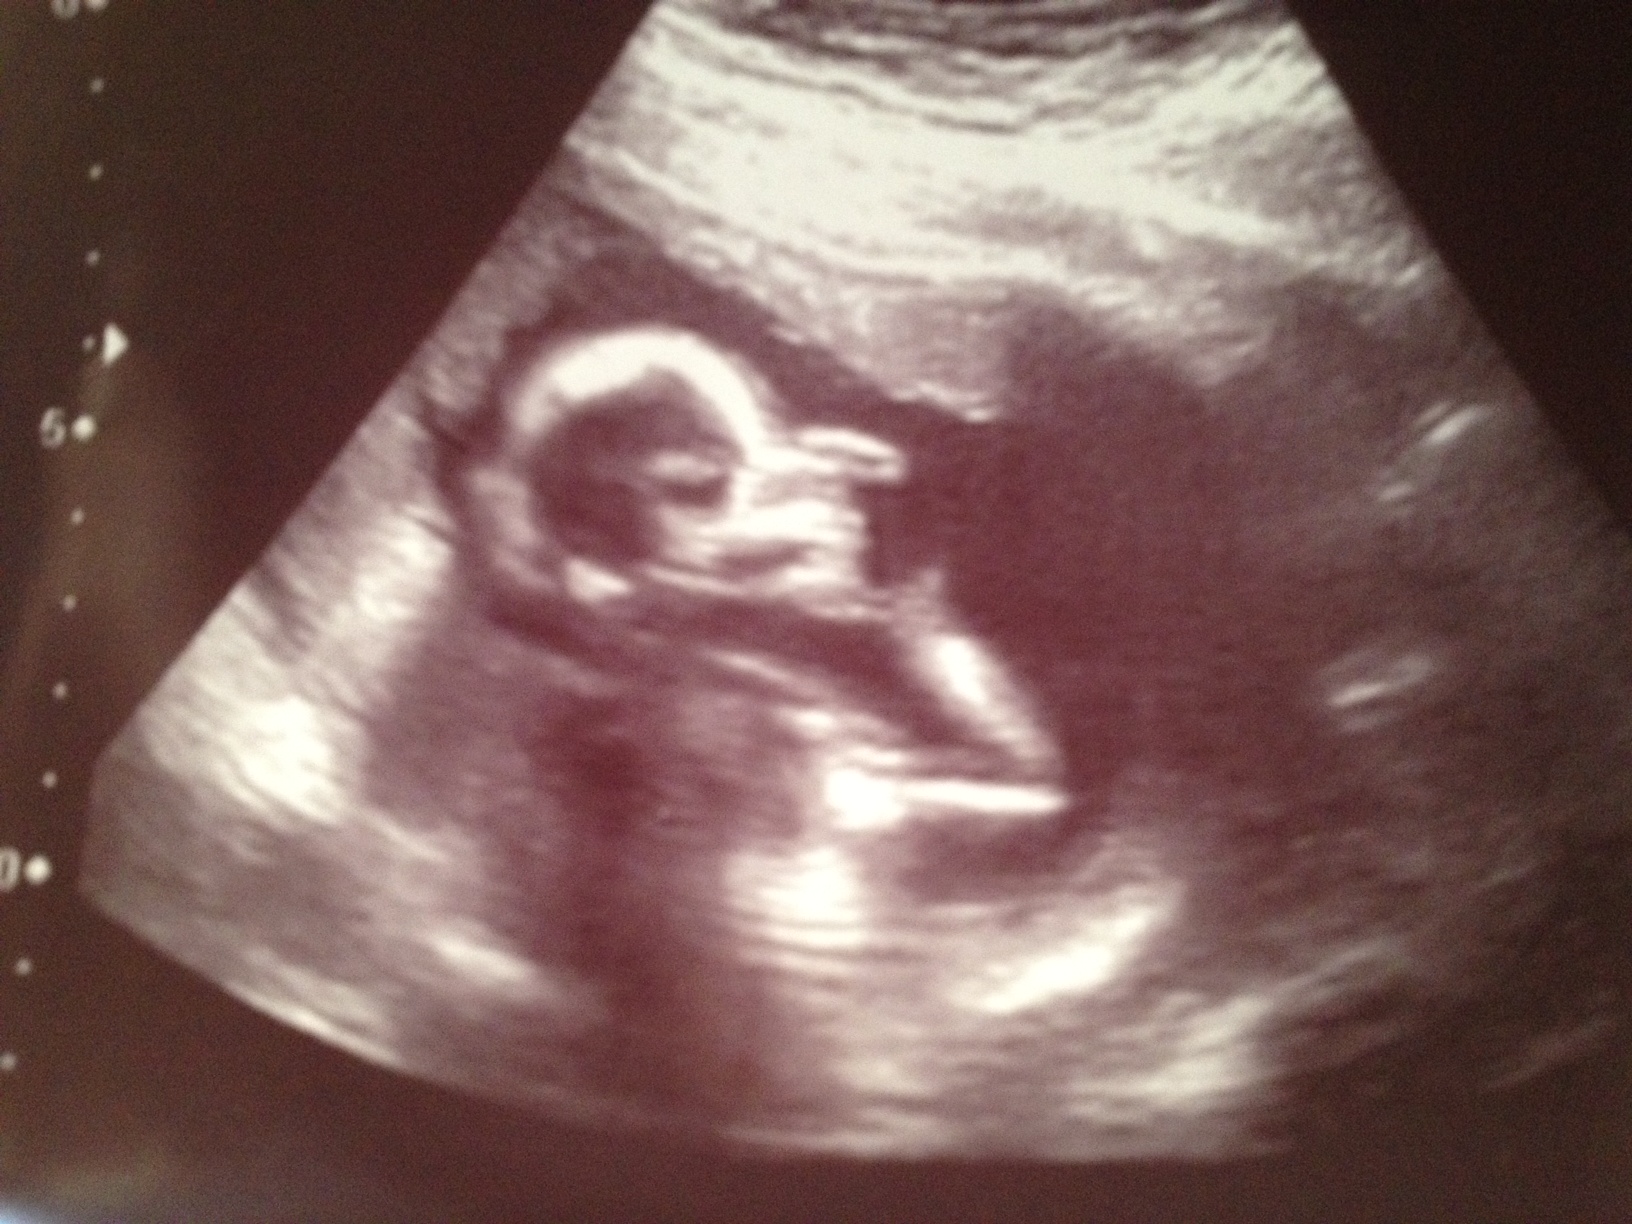

¡Es una niña!

Se acabaron las dudas. Es el bebé de casi 20 centímetros más guapo del mundo, pesa unos 200 gramos y es una niña. Hoy me han hecho una revisión por las 18 semanas de embarazo y al fin se ha descubierto el misterio.

Finalmente ha ido saliendo de su refugio poco a poco y el ginecólogo ha dado su sentencia: es una niña.

Hace mucha ilusión y mas como mujer pensar en criar una niña, la próxima generación, pero de verdad que esta noche dormiré bien porque lo tiene todo en su sitio. Las ecografías son el mejor invento del mundo. He visto sus pies, sus brazos (son muy largos), el cordón umbilical e incluso los riñones. Ahora la tranquilidad te invade y solo quedan cinco semanas para verla de nuevo…